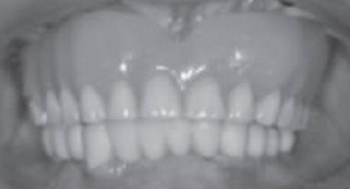

根據(jù)所得信息將制定16、13、23及26為種植體位置行all-on-4種植手術。種植手術:常規(guī)消毒、鋪巾,甲哌鹽酸阿替卡因局部浸潤局麻下,患者戴上去除牙膠并已消毒后的放射模板,在16、13、23及26位置用球鉆定位(圖9、10、11、12),行微創(chuàng)切口(圖13),從17至12和從27至22的切口,并在所定位置逐級備洞,分別在13、16、23及26各植入一枚Nobel Replace Conical Connection 4.3mm*13mm種植體,同時在13、23接30°復合基臺,在16、26接復合直基臺(圖14)。嚴密縫合后行即刻修復(圖15、16、17、18)。

術后曲面斷層全景片(圖19)可見種植體在上頜位置較為理想,同時可見臨時義齒種植體開孔位置在13、23舌側、16、26牙合面近中,上下頜咬合關系理想。患者對種植臨時修復義齒滿意。